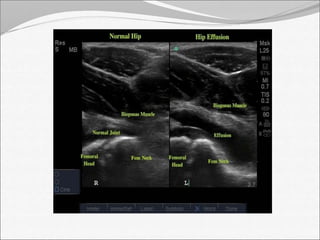

Ultrasonography

 More reliable in revealing a joint effusion in early

cases.

 Widening of space between capsule and bone of

>2mm indicates effusion.

 Echo free  transient synovitis

 Positively echogenic  septic arthritis

 Ultrasound can detect joint-swelling.

Being a non- ionizing, easily available, non-invasive

and relatively cheap modality, Ultrasound should be

first line of investigation in a suspected case of

infective arthritis.

Ultrasonography  Morereliable in revealing a joint effusion in early cases.  Widening of space between capsule and bone of >2mm indicates effusion.  Echo free  transient synovitis  Positively echogenic  septic arthritis  Ultrasound can detect joint-swelling.

Being a non-ionizing, easily available, non-invasive and relatively cheap modality, Ultrasound should be first line of investigation in a suspected case of infective arthritis.